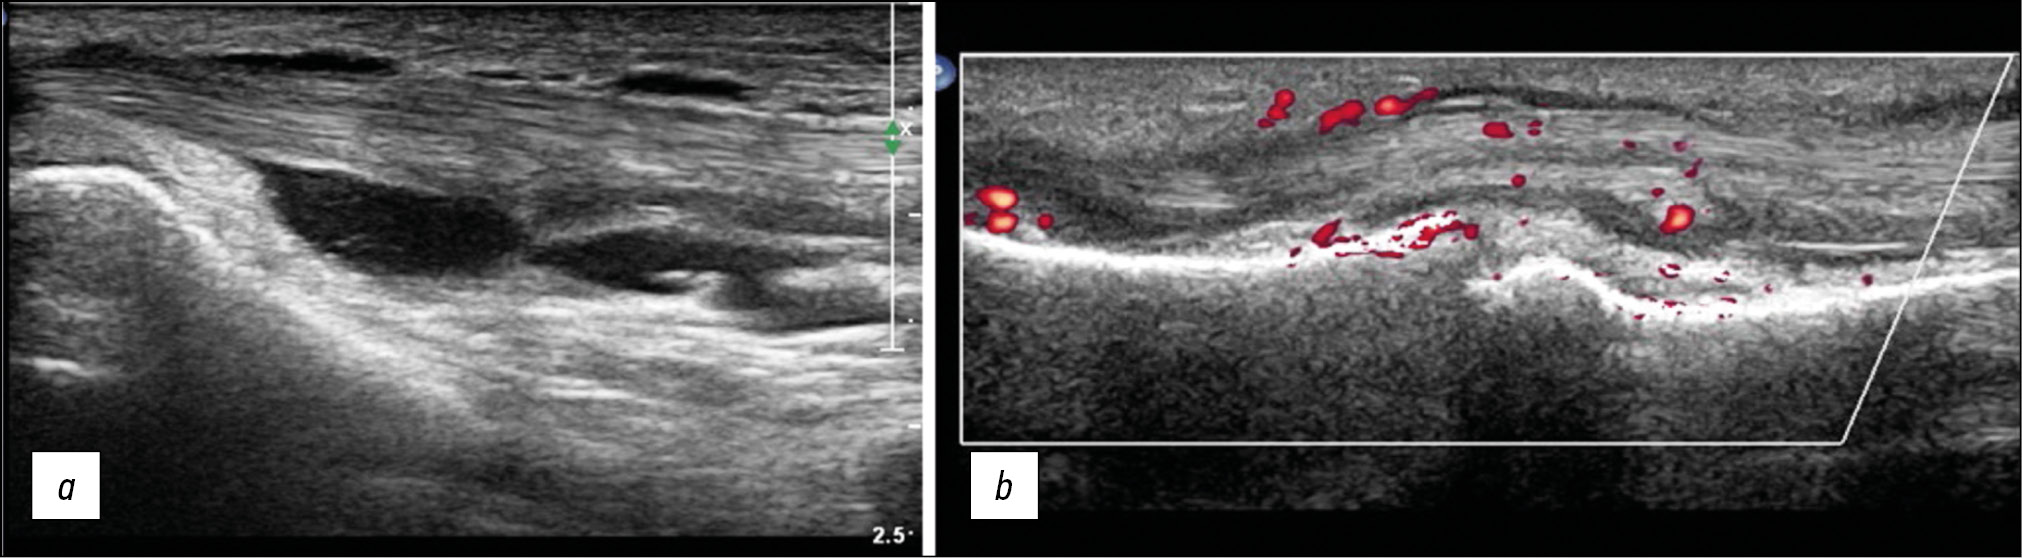

Fig. 5. Longitudinal sonogram of tenosynovitis of the tendons of the long flexors of the second finger of the foot (a) and the flexor tendons of the third finger of the hand (b). Signs of tenosynovitis on ultrasound are similar in both cases and are characterized by thickening of the tendon, fluid in the synovial membrane, and hypertrophy of the synovial wall of the tendon sheath. Using the color Doppler imaging mode, blood flow in the synovium is observed .

IL-1β, IL-17, and TNF-α can disrupt the normal biological activity of tenocytes and contribute to the onset of tendon disorders, which cause potential exacerbation of degenerative tendon diseases and the related inflammatory processes [2] (Fig. 5).